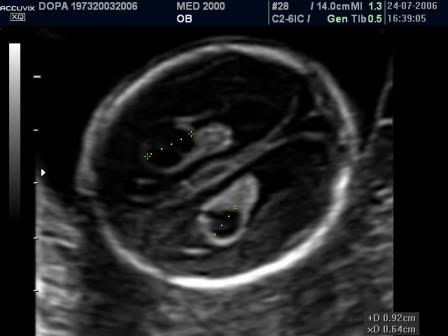

Ecograficamente si presentano come aree cistiche rotondeggianti o ovalari, uniloculari o settate, di diametro variabile da 3 a 9 mm., singole o multiple, monolaterali o bilaterali, localizzate più frequentemente nei plessi corioidei dei ventricoli cerebrali laterali, meno frequentemente nel III e IV ventricolo.